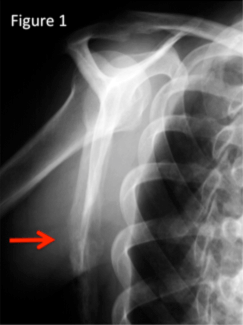

MRgFUS is performed on an outpatient basis so that patients can return to normal activities within a few days. The procedure is performed with the patient lying on the stomach or on the back in an MRI scanner for three to five hours under conscious sedation. An ultrasound probe is located under or over the site of the bone metastasis, and a water bath or gel is used to maximize acoustic contact between the skin and the ultrasound transducer. While the patient may feel some pain during the procedure, it should only be mild, and an anesthesiologist will administer medications to make the patient feel as comfortable as possible throughout the procedure.

The ultrasound probe generates high intensity waves that focus on the bone metastasis and cause the temperature in the bone and metastasis to rise. The result is cellular death in the area of the focused ultrasound, which effectively inactivates the nerve endings that generate the pain. During the procedure the temperature is constantly measured and the treated area is carefully monitored.

Figure 2 shows the set-up for a MRgFUS bone metastasis treatment with the patient lying on the ultrasound probe (Courtesy Insightec, Inc).